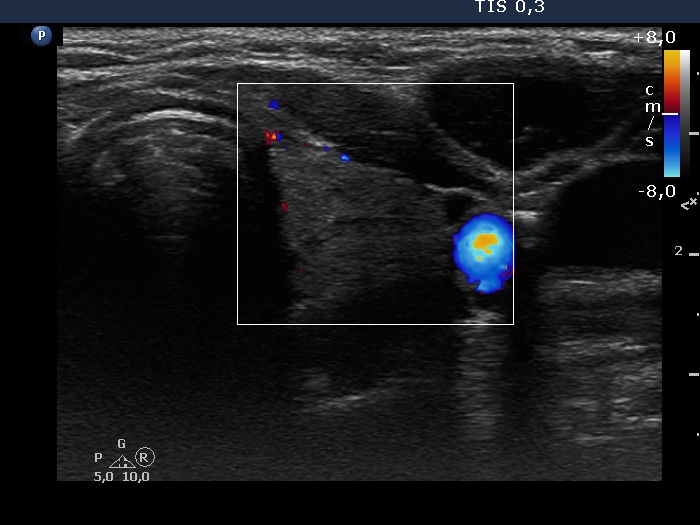

Right lobe, longitudinal scan

Left lobe, transverse scan, color Doppler mode. The vascularization is decreased.